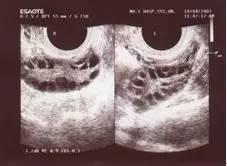

3、多囊卵巢是指卵巢形态学的改变,表现为卵巢体积增大,B超检查时可见多个不成熟的小卵泡呈串珠状包绕于卵巢周边,俗称“项链征”,它是多囊卵巢综合症特有的临床表现之一。